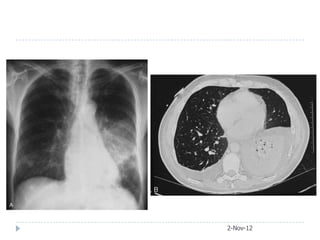

• #33 A, Legionellosis, initial chest radiograph showing left lower lobe consolidation.B, Legionellosis, initial chest computed tomography demonstrates left lower lobe alveolar infiltrate and pleural effusion.

• #34 B, Legionellosis, initial chest computed tomography demonstrates left lower lobe alveolar infiltrate and pleural effusion. C, Legionellosis, chest computed tomography performed 6 weeks later (and after a 3-week course of macrolide) demonstrates partial resolution of left lower lobe alveolar infiltrate and disappearance of parapneumonicpleural effusion.